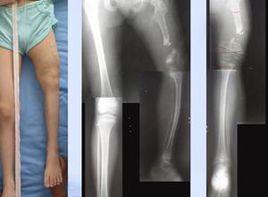

①症狀:A.關節活動障礙:患肢常呈屈曲狀活動較健側差蹬踩力量位於另一側髖關節外展受限。B.患肢短縮:患側股骨頭向後上方脫位常見相應的下肢短縮。C.皮紋及會陰部的變化:臀部及大腿內側皮膚皺褶不對稱患側皮紋較健側深陷,數目增加女嬰大陰唇不對稱會陰部加寬。

①症狀:A.跛行步態:跛行常是小兒就診時家長的惟一主訴。一側脫位時表現為跛行;雙側脫位時則表現為鴨步,患兒臀部明顯後突腰前凸增大。B.患肢短縮畸形:除短縮外同時有內收畸形。

①先天性發育不良:股骨頭僅略向外移,Shenton線基本正常但CE角可減小,髖臼變淺,Dunn稱此為先天性髖關節脫位Ⅰ級。

②先天性半脫位:股骨頭向外上方移位,但仍與髖臼的外側部分形成關節,Shenton線不連續,CE角小於20deg;,髖臼變淺屬Dunn分類Ⅱ級。

③先天性完全脫位:股骨頭完全在真性髖臼以外,與髂骨的外側面形成關節,逐漸形成假髖臼,原關節囊則嵌夾於股骨頭與髂骨之間屬Dunn分類Ⅲ級。

①Ⅰ度脫位:股骨頭骺核位於Y線以下、髖臼外上緣垂線之外。

②Ⅱ度脫位:股骨頭骺核位於Y線與Y線的臼上緣平行線之間。

③Ⅲ度脫位:股骨頭骺核位於臼上緣平行線高度。

④Ⅳ度脫位:股骨頭骺核位於臼上緣平行線以上,並有假臼形成。